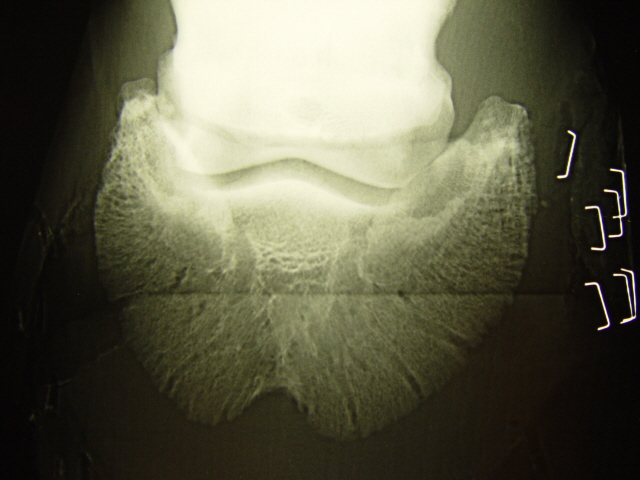

Röntgenaufnahme des Hufbeins

Einkerbung an der Hufbeinspitze und Atrophie der Hufbeinäste